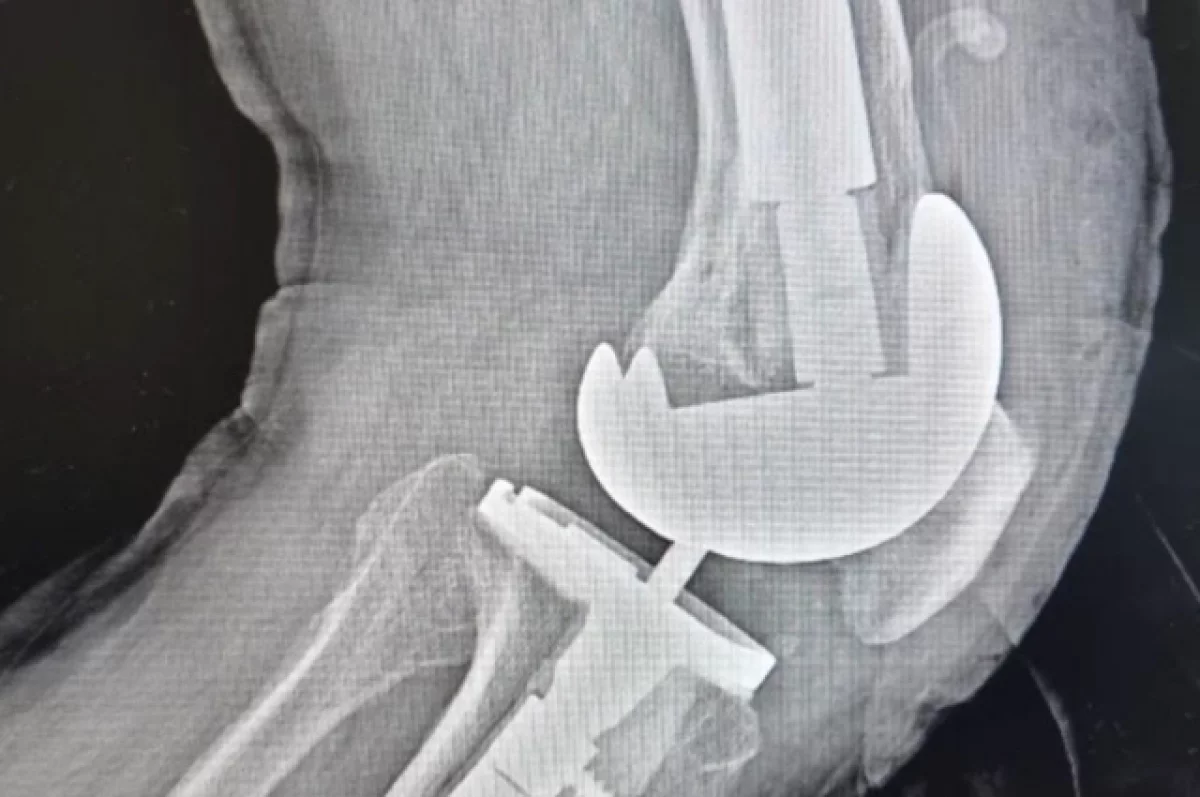

Врачи мурманской «Пироговки» впервые провели ревизионное эндопротезирование коленного сустава 75-летнему мужчине из Апатитов.

Заведующий отделением травматологии и ортопедии ММЦ имени Н.И. Пирогова ФМБА России Сергей Боженко пояснил, что «ревизия» — это сложная операция по замене установленного ранее протеза сустава на новый.

«Сложность в том, что при удалении протеза всегда возникает дефицит костной ткани, который нужно заполнить специальными компонентами», — рассказал врач Боженко.